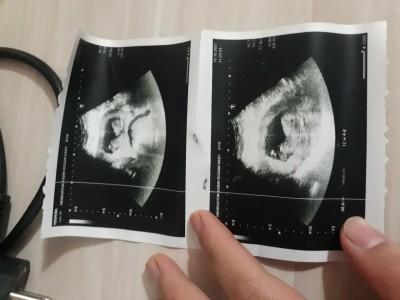

kızlar cinsiyet tahmini yaparmisiniz burda  12hafta 4 günlük

Gebelik haftası 13